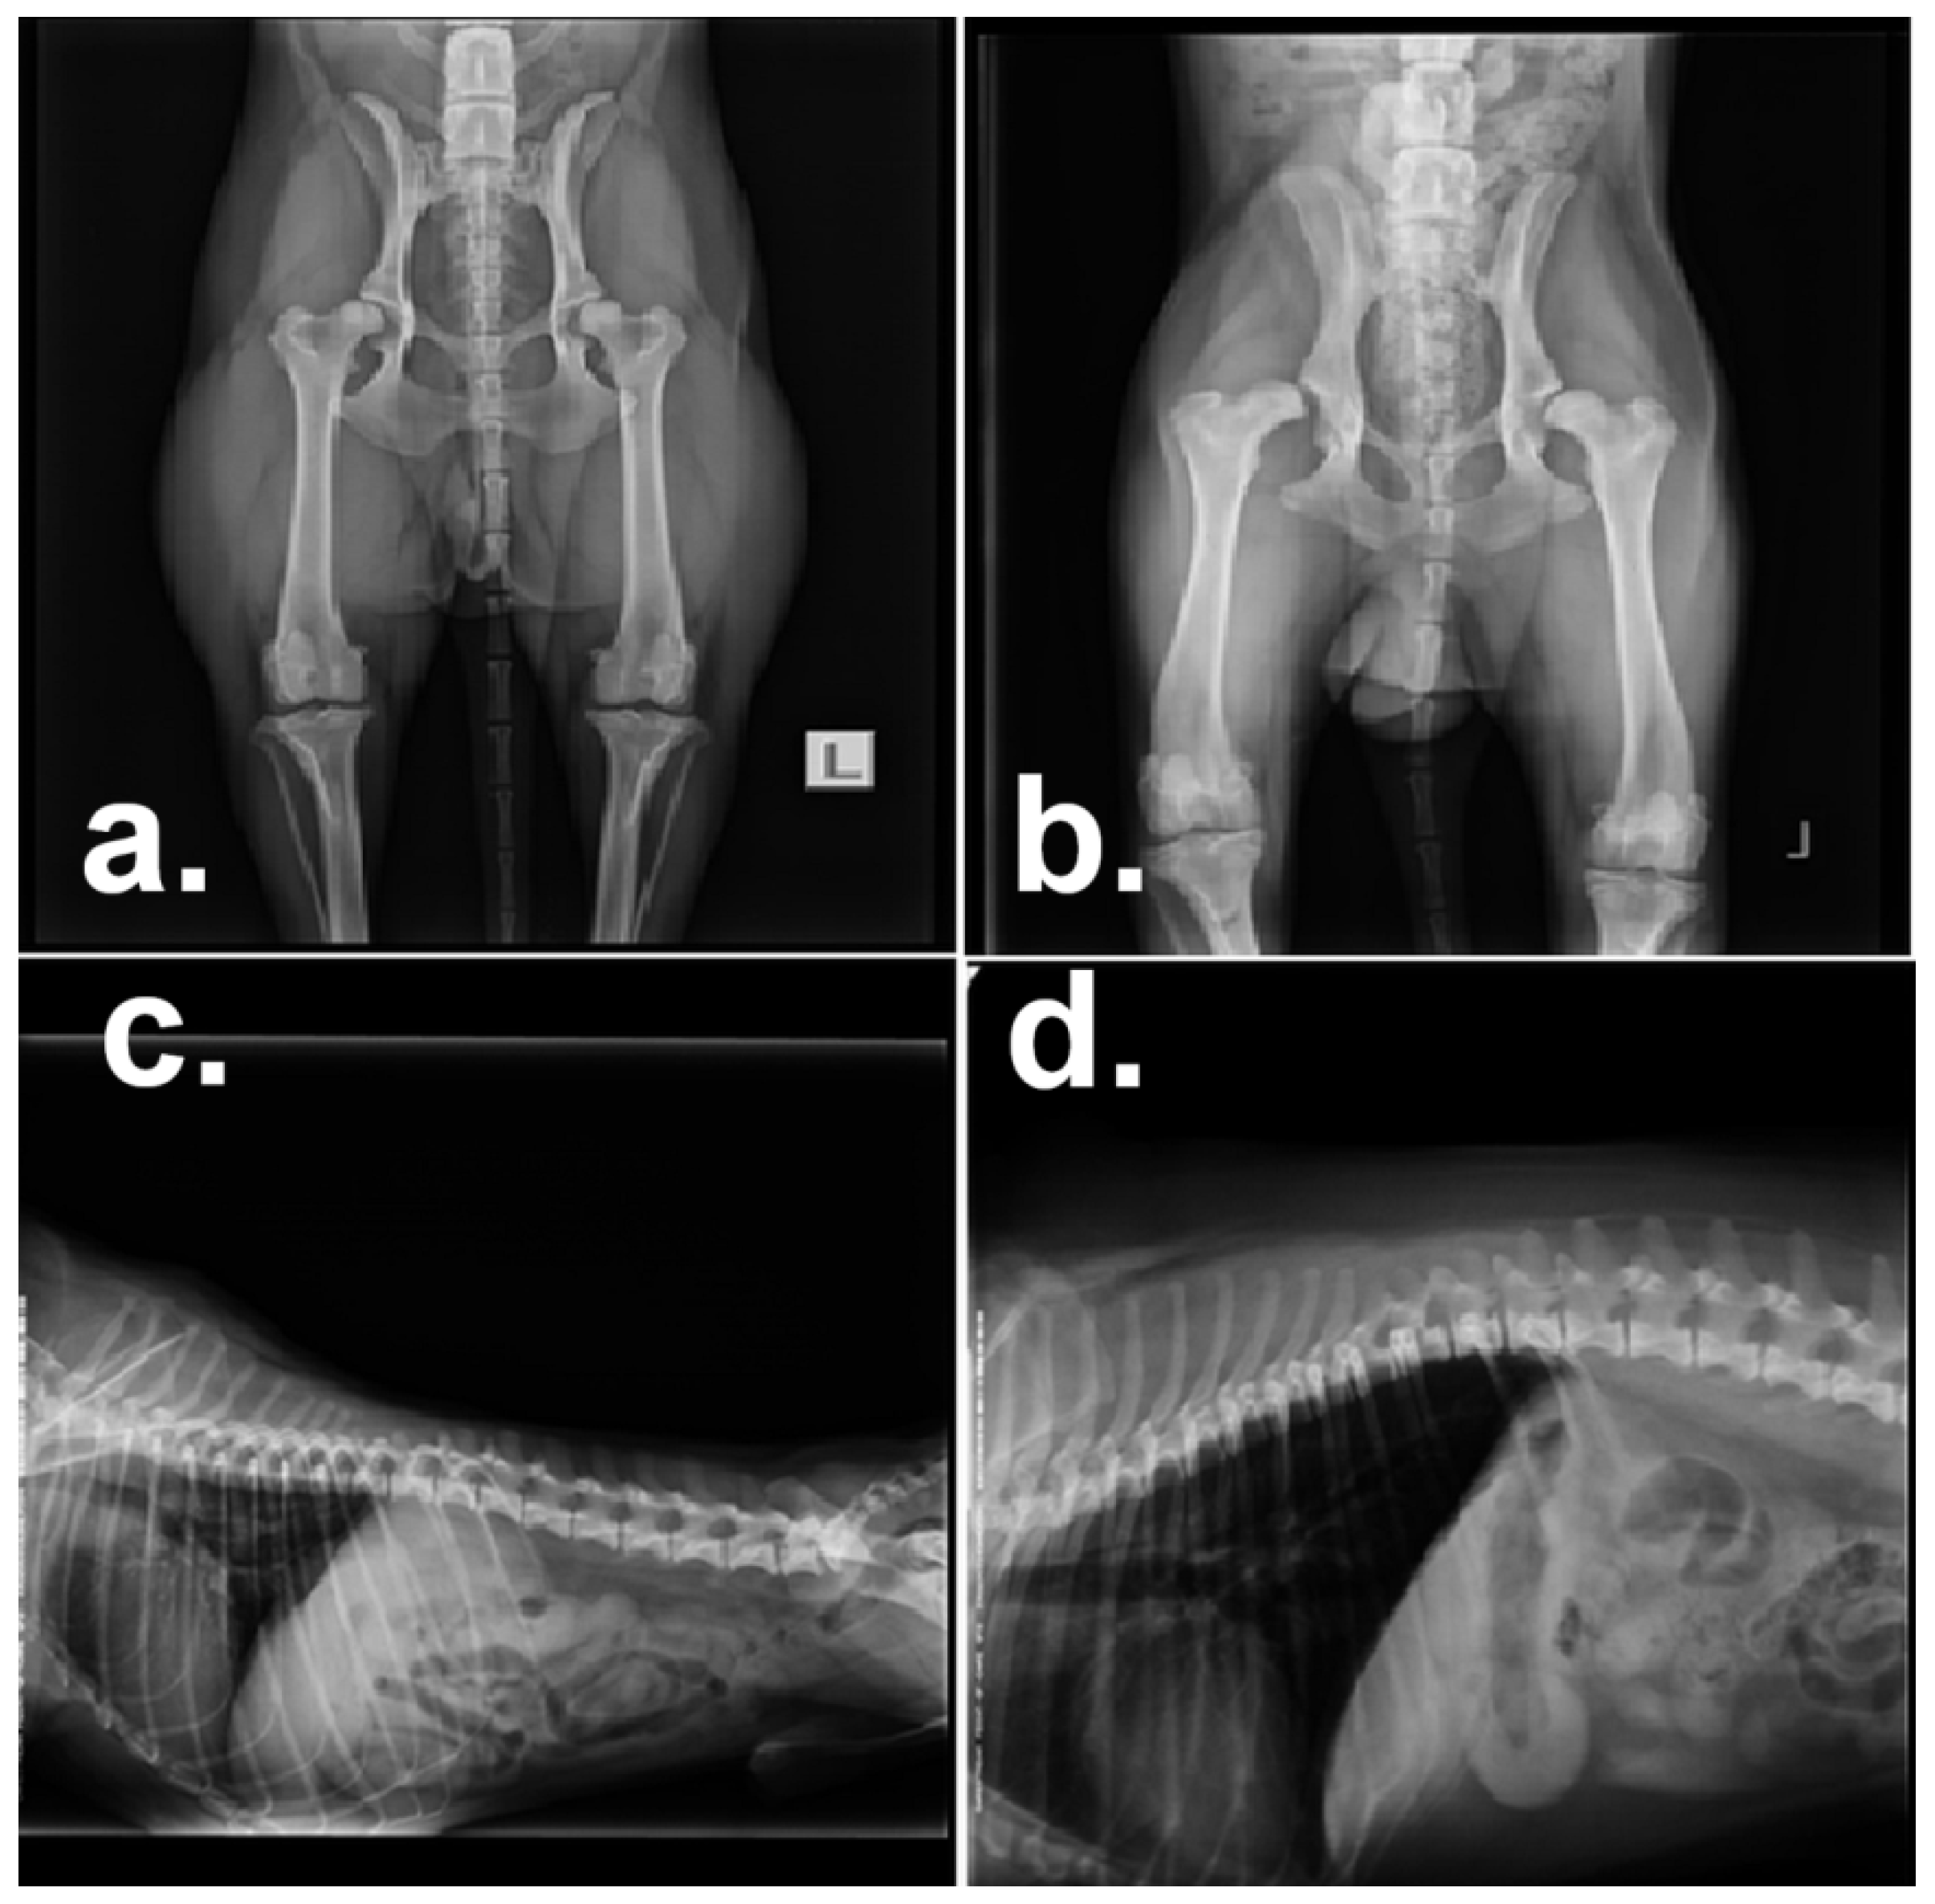

| 4 | Mixed breed Labrador-Sain-Bernard, male | Hip dysplasia grade 2–3 on the right, grade 1 on the left, moderate pain in the spine. Physiotherapeutic evaluation: mild chronic pain with activation at T13-L1 level. | Electrotherapy (ET)—amplitude modulated current 4000 Hz, hydrotherapy, laser. Laser F-L: NogC, 2J 10 sessions. ET 100–250 Hz, 16 mA at the spine T13-L1. ET 1-250, 4.4 KHz, 14.5 mA the whole spine. Hydrotherapy with hip-high water level: Session S1: 100 m walk, 2× break with knee-high water level. S2: 0.6 km/h slow walk, 170 m. S3: identical S4: 0.8 km × h−1, 425 m. S5: identical. S6: 0.7 km × h−1, 470 m. S7: identical. S8: 0.8 km × h−1, 540 m. S9: 0.8 km × h−1, 700 m. S10: identical. |